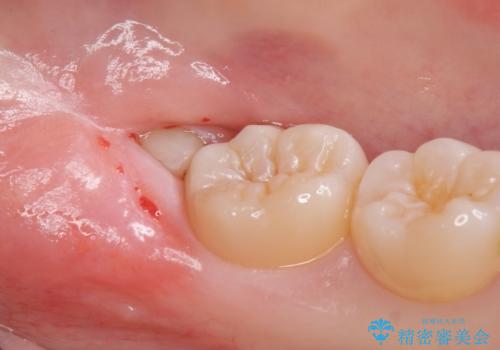

抜歯後、1週間後に抜糸を行う必要があります。

無事に親知らず抜歯ができました。

次回反対側の親知らずを抜歯するか検討中です。